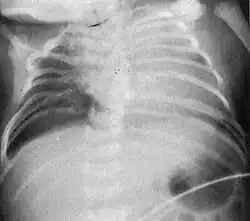

| Radiograph depicting typical skeletal features of Jarcho-Levin syndrome, subtype spondylothoracic dysplasia. Note fanlike configuration of the ribs, with extensive posterior fusion, along with multiple vertebral segmentation defects. | |

Spondylothoracic dysplasia, or STD, has been repeatedly described as an autosomal recessively inherited condition that results in a characteristic fan-like configuration of the ribs with minimal intrinsic rib anomalies. Infants born with this condition typically died early in life due to recurrent respiratory infections and pneumonia due to their restricted thorax.[3][4][5] Recently, a report[6] has documented that actual mortality associated with STD is only about 50%, with many survivors leading healthy, independent lives.